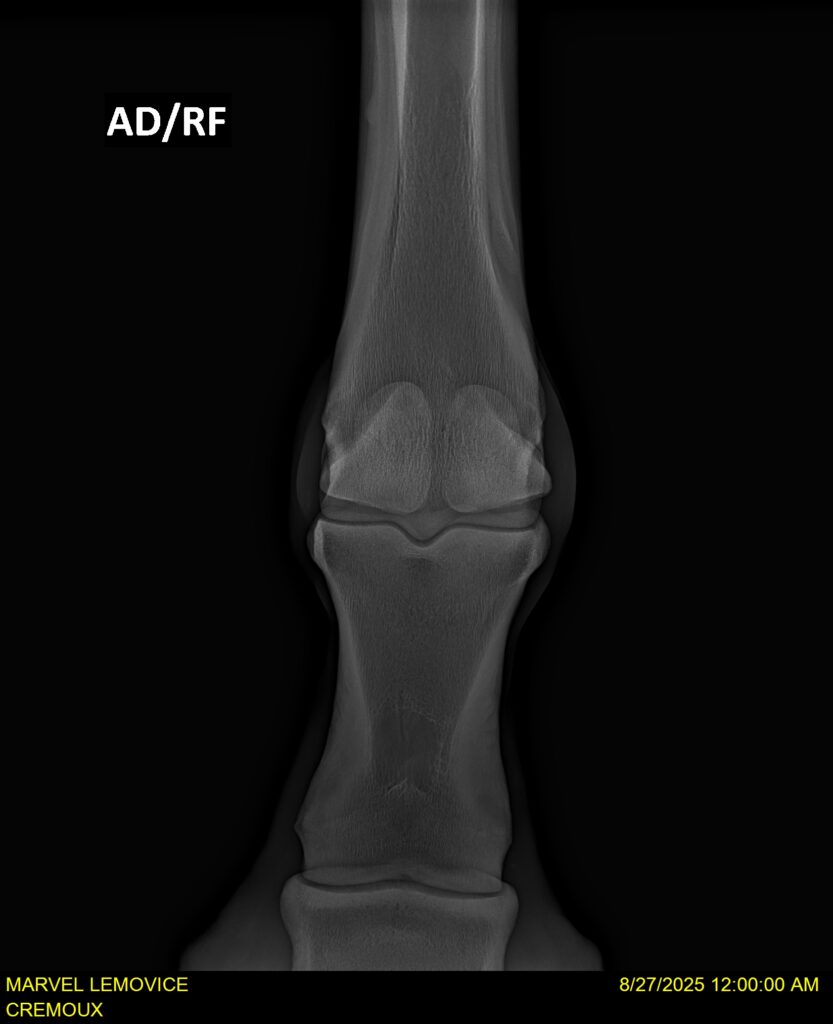

MARVEL LEMOVICE, hongre, Selle Français prend 4 ans en 2026. POPSTAR LOZONAIS x ROSIRE sur une excellente souche maternelle de l’élevage PLATIERE. Débourré aux trois allures et mise en route à l’obstacle. Super modèle avec du cadre et de la force, cheval respectueux avec des moyens. Très agréable au quotidien. Transport OK, maréchalerie OK, santé RAS, Bilan 20 clichés radios + clinique OK.

RADIOS ET CLINIQUE